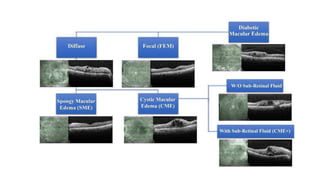

Diabetic maculopathy

• Most common cause of visual impairment in diabetic patients

and is due to foveal affection by edema, hard exudates or ischemia. It

is classified into

• a. Focal macular edema

• b. Diffuse macular edema

• c. Ischemic maculopathy

• d. Mixed type